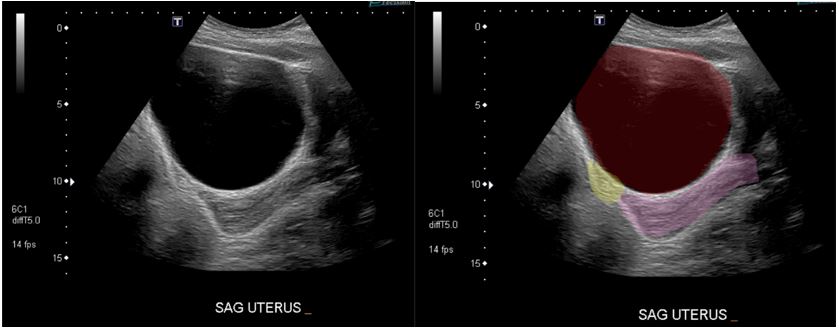

A 13-year-old previously healthy female with no past medical history presented with 4 days of right lower quadrant pain. She had complete resolution of her pain after Motrin and a benign abdominal exam, so she was discharged home. She returned 4 days later with right lower quadrant pain, nausea, and vomiting that had reoccurred at 4 am that morning. A point-of-care ultrasound (POCUS) was performed and showed a normal bladder and no hydronephrosis. She had a normal transabdominal pelvic ultrasound for torsion and a non-diagnostic appendix ultrasound performed by radiology (Figure 1).

Figure 1: Transabdominal Ultrasound. Red: Hemorrhagic Hydrosalpinx; Pink: Uterus; Yellow: Bladder